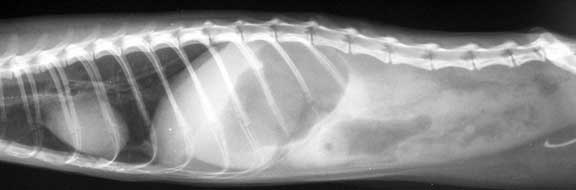

This ferret is lying on its right side, with the heat at the left

The arrow points to the circular FB on the lateral view in the same location. Note the dark area that says small intestine. This dark area is gas, because the foreign body is causing an ileus, and the intestine is filling up with gas and distend because the normal peristalsis is interrupted.